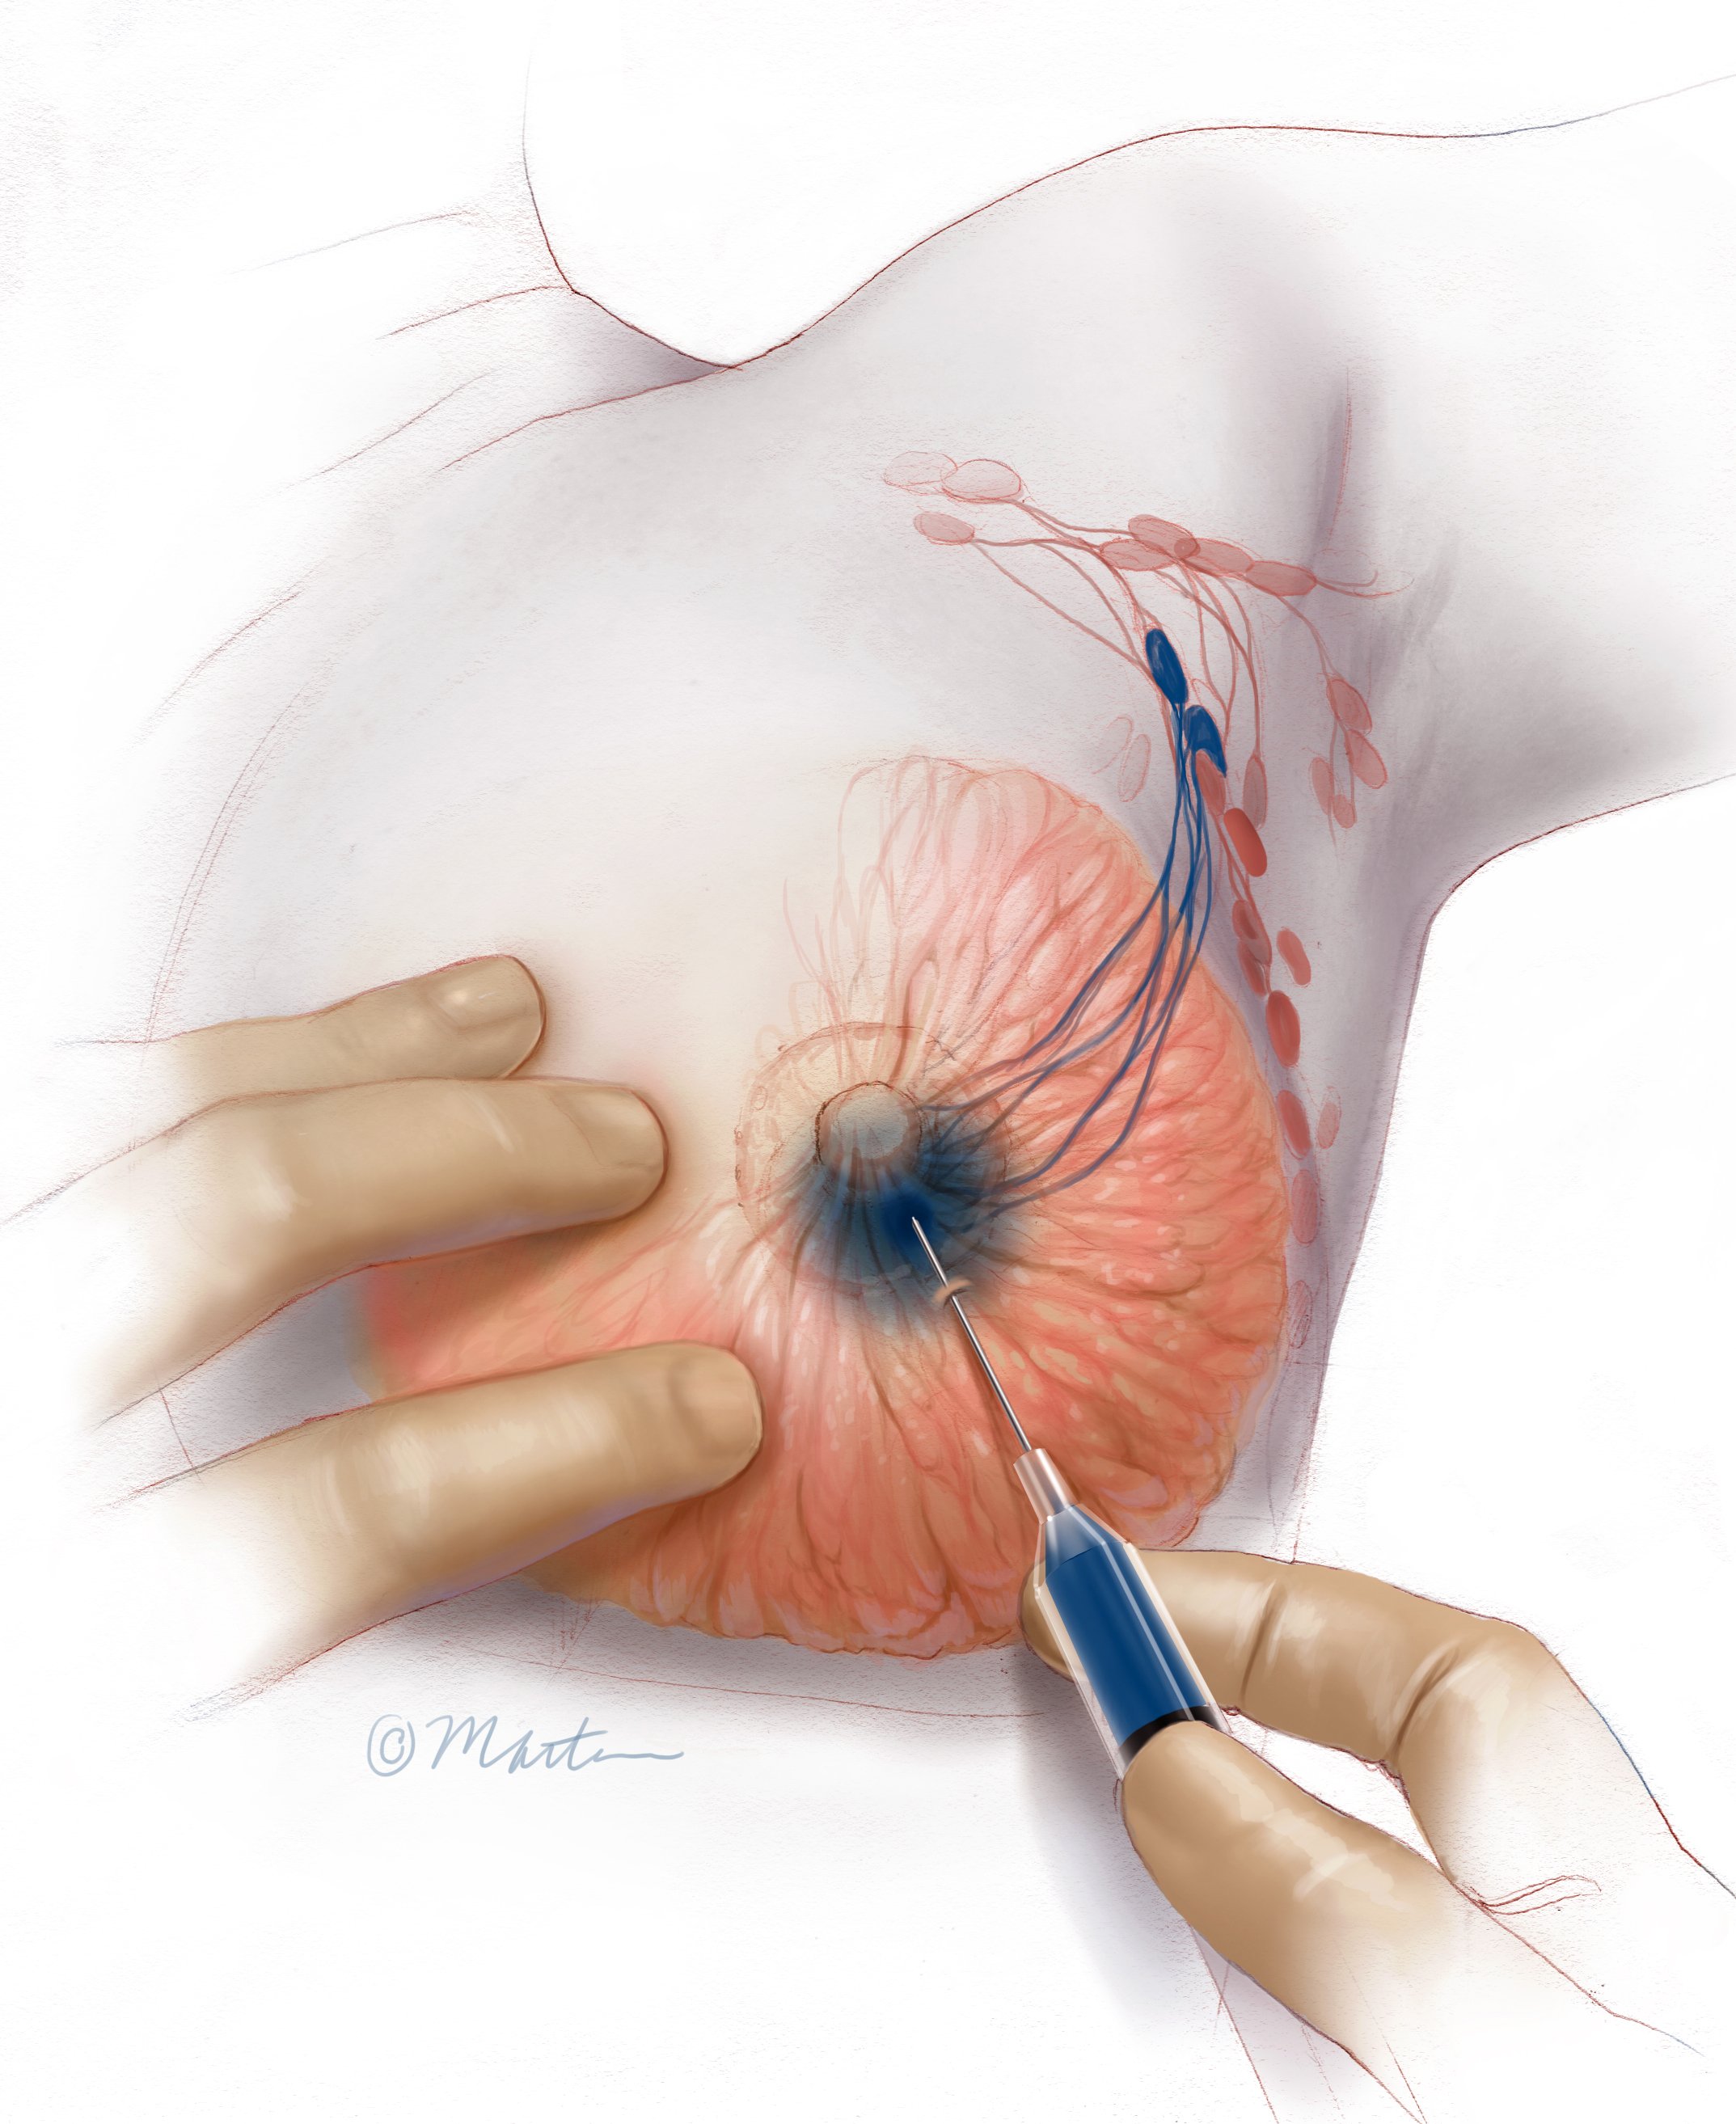

Sentinel Node